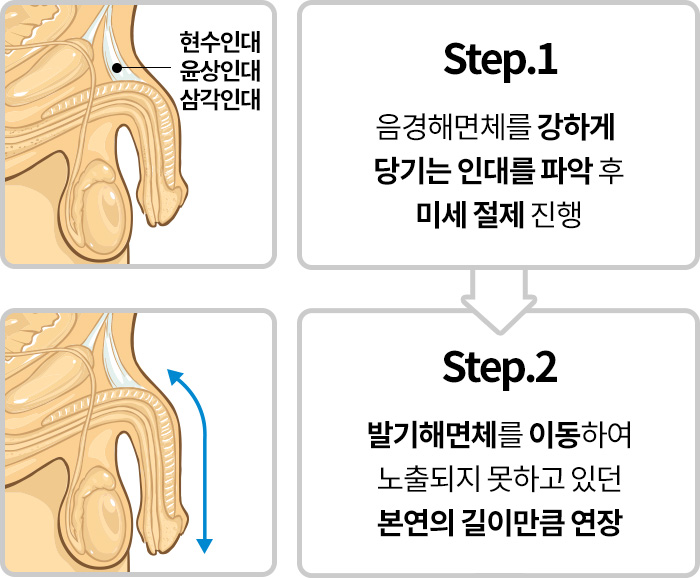

음경인대견인

성기의 인대가 과하게 발달하여

성기가 몸 안쪽으로 숨어 있는 경우

음경인대견인

강한 인대에 의해서 외부로

충분히 노출되지 못하고 있으므로

음경 근위부(성기 뿌리쪽) 인대 절제 후

발기 해면체를 이동하여 길이를 연장

*유착방지 처리로 재견인 예방